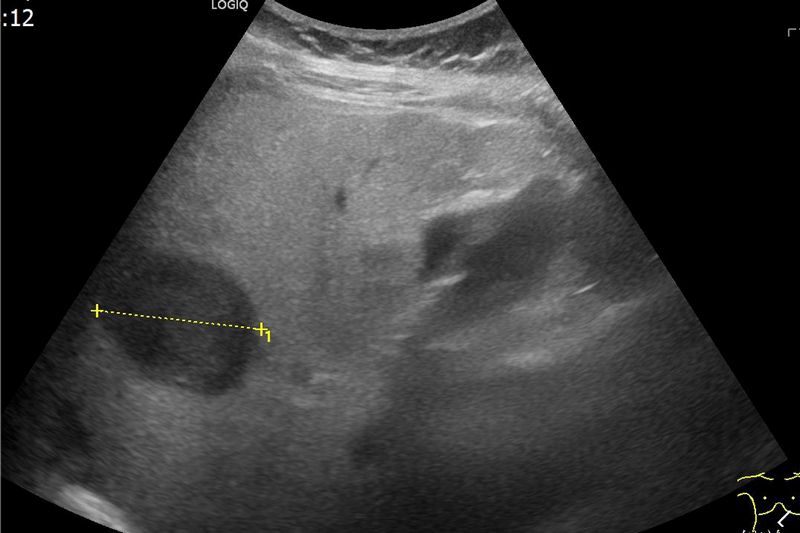

【記者盧世光/綜合報導】年近八旬的許奶奶患有慢性肺病、心臟衰竭、糖尿病、高血壓等多種慢性疾病,長期於台北慈濟醫院胸腔內科及感染科追蹤看診。半年前回診發現肝指數過高,感染科醫師遂安排腹部超音波檢查,結果發現脂肪肝及肝臟一顆約三公分大腫瘤,故轉診至胃腸肝膽科陳泓達醫師門診進一步檢查。後續經由電腦斷層、磁振造影檢查,診斷為肝癌,陳泓達醫師考量許奶奶肝功能及身體狀況執行「腫瘤射頻燒灼術」,術後三天,許奶奶平安出院。

肝癌的診斷除了觀察臨床表現外,還需藉由抽血檢查檢驗肝功能狀態,並利用腹部超音波、電腦斷層或核磁造影等相關檢查確認腫瘤型態、大小以及是否有轉移。在手術治療方面,除了傳統開腹手術、微創腹腔鏡或達文西手術外,尚有腫瘤射頻燒灼術的選擇,主要運用於腫瘤小於2至3公分的患者或心肺功能無法負荷麻醉或手術風險較高的病患;腫瘤大於3公分以上的患者是否適用則需醫師詳細評估。以許奶奶為例,慢性疾病較多、身體機能較差,經多團隊會議及家屬溝通後,射頻燒灼術治療是最妥適的選擇。首先以超音波定位確認病灶,再以電燒針穿刺至腫瘤中央,在腫瘤內產生高熱使癌細胞壞死,達到治療目的。陳泓達醫師提到:「射頻治療的治療時間約落在數十分鐘左右,對病人的影響較輕,在審慎評估後適用的病患族群預後效果與其他手術相當,是肝癌治療的另一種選擇。」